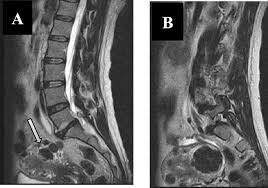

In the lower cavity there is stomach, liver, gallbladder and the intestines. For instance, intervertebral discs rarely bulge exactly in the centre, but to one side or the other. Normally, the pelvic organs—the bladder, uterus, vagina, and rectum—are supported and held in place by a group of muscles and tissues called the pelvic floor. From there, bacteria can cause damage to the kidneys, resulting in reduced kidney function. A herniated disk, or arthritis in the lower back can also cause aching pains.